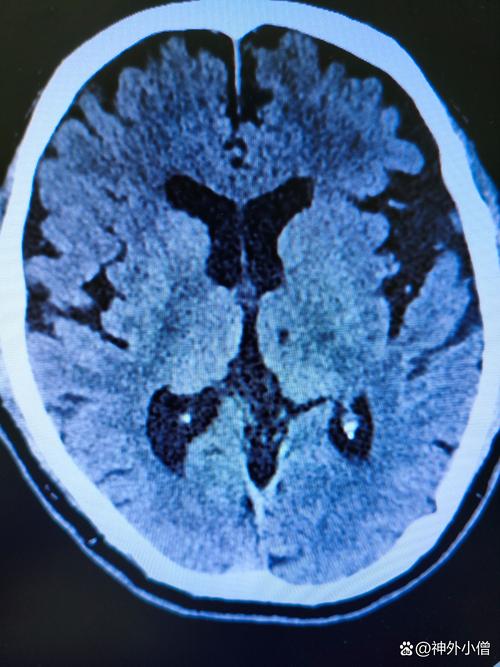

- 快速诊断:通过头颅CT(首选,能快速排除脑出血)或MRI来确诊脑梗。